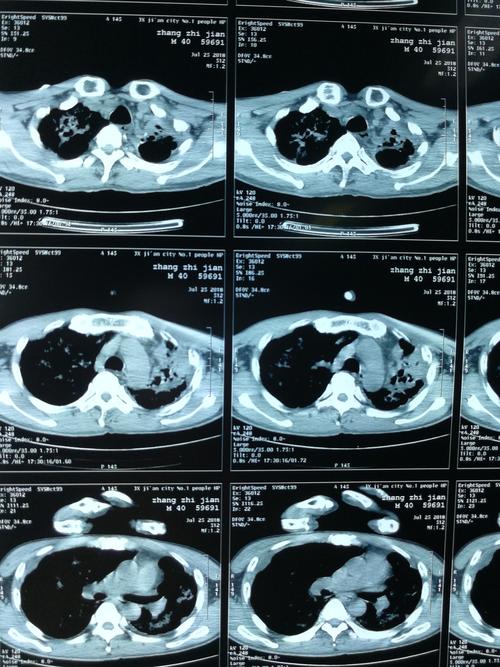

肺部感染ct图片

肺部感染片子

肺部感染胸片

肺部感染ct

肺部感染图片

严重肺部感染ct图片

肺部感染片子图片

肺部感染拍片图片

肺部感染图片真实

肺部感染的ct影像图片